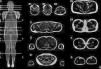

Resonancia magnética de cuerpo completoEl examen de resonancia magnética fue realizado en un equipo 1.5 T Avanto Siemens. Los pacientes fueron posicionados en decúbito supino. Se utilizaron 2 bobinas Body Array y una bobina de extremidades inferiores. El protocolo estándar incluyó localizadores HASTE en planos axial, coronal y sagital, ajustado al tamaño del paciente (fig. 2), con adquisiciones con GRAPPA, 4 bloques secuenciales de imágenes T1w Turbo Spin Eco (FOV de lectura 280-360mm, TR 477ms, TE8,4ms, cortes de 4mm, matriz 512×281, 1.00NEX); bloques secuenciales de 25 cortes de 4mm con secuencia Dixon de 3 puntos, (FOV de lectura 360mm, TR 571ms, TE 11ms, matriz 512×358 interpolada 2.00NEX) en la región masticatoria, cintura escapular, región toracoabdominal, cintura pélvica, muslos, y piernas, con un tiempo total de examen aproximado de 30min (fig. 3).

Con la secuencia Dixon de 3 puntos22, obtuvimos 4 imágenes simultáneamente: dentro de fase, fuera de fase, imagen de agua e imagen de grasa. Se estimó la señal de la grasa de acuerdo a la siguiente ecuación:

Análisis de las imágenes y cuantificaciónLas imágenes fueron evaluadas en conjunto por 3 observadores. Se evaluaron 54 músculos diferentes. Para los músculos orientados perpendicular al eje axial (30/54), se realizaron 5 mediciones (ROI) en 3 segmentos (proximal, medio y distal) a lo largo del músculo, y un ROI del área de sección; para aquellos con fibras predominantemente orientadas en el plano axial (24/54), se realizaron 5 mediciones en el espesor principal del músculo y un ROI del área de sección.